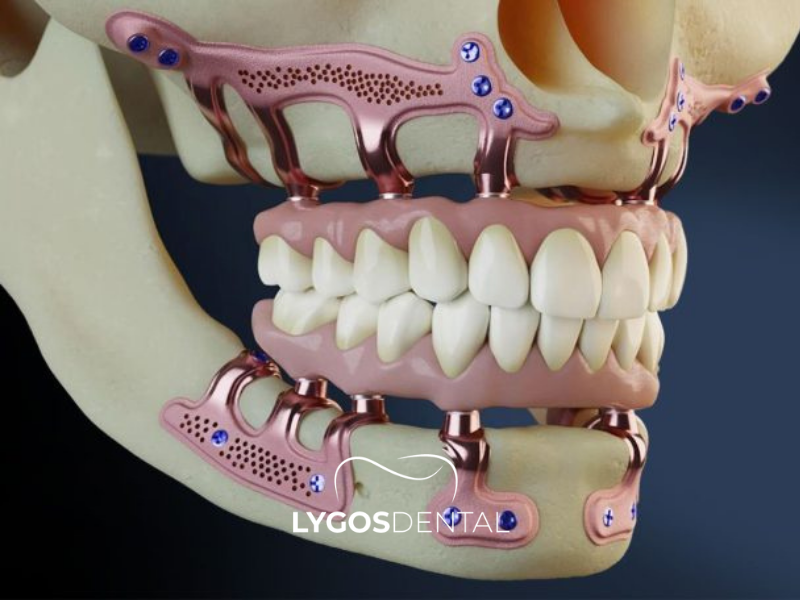

Subperiostal implant, çene kemiğinin üzerine yerleştirilen ve diş protezlerini desteklemek için kullanılan özel bir implant türüdür. Bu implant türü, kemik içine yerleştirilen klasik implantlardan farklıdır. Metal bir çerçeve, çene kemiğinin üst kısmına konumlandırılır.

Diş eti dokusu iyileştikten sonra çerçevenin uçları ağız içinde görünür hale gelir. Bu uçlara sabit diş protezleri yerleştirilir. Genellikle çene kemiği hacmi yetersiz olan hastalarda tercih edilir. Subperiostal implant, kemik içine implant yerleştirmenin zor olduğu durumlarda alternatif bir tedavi seçeneği sunar.

Subperiostal İmplant ile klasik implant arasındaki en temel fark, implantın kemiğe yerleşim biçimidir. Klasik implant sistemlerinde implant, çene kemiğinin içine yerleştirilir ve zaman içinde kemikle bütünleşmesi beklenir. Subperiostal İmplant sisteminde ise taşıyıcı yapı kemiğin içine değil, kemiğin üzerine konumlandırılır ve diş eti altından destek alınır.

Subperiostal İmplant tedavisinde öncelikle çene yapısına uygun özel bir planlama yapılır. Tedavinin mantığı, kemiğin yüzeyine uyum sağlayacak bir taşıyıcı sistemin hazırlanmasına dayanır. Bu yapı, diş eti altına yerleştirilir ve ağız içinde protezi taşıyacak destek noktaları bırakılır. Böylece ileri kemik kaybı bulunan bölgelerde, kemiğin içine yerleştirilen klasik implantlara alternatif bir destek mekanizması oluşturulur. Uygulama sürecinin başarısı, sistemin çene kemiğiyle uyumlu biçimde tasarlanmasına ve yumuşak dokularla dengeli şekilde ilişkilendirilmesine bağlıdır.

Subperiostal İmplant yalnızca cerrahi bir yerleştirme işlemi değildir. Aynı zamanda protez planlaması ile birlikte düşünülmesi gereken çok aşamalı bir süreçtir. Çünkü ağız içine uzanan destek noktalarının yeri, gelecekte kullanılacak sabit ya da hareketli üst yapının başarısını doğrudan etkiler. Bu nedenle tedavi, yalnızca implant yerleştirmek değil, aynı zamanda fonksiyonel bir protez altyapısı hazırlamak anlamına gelir.